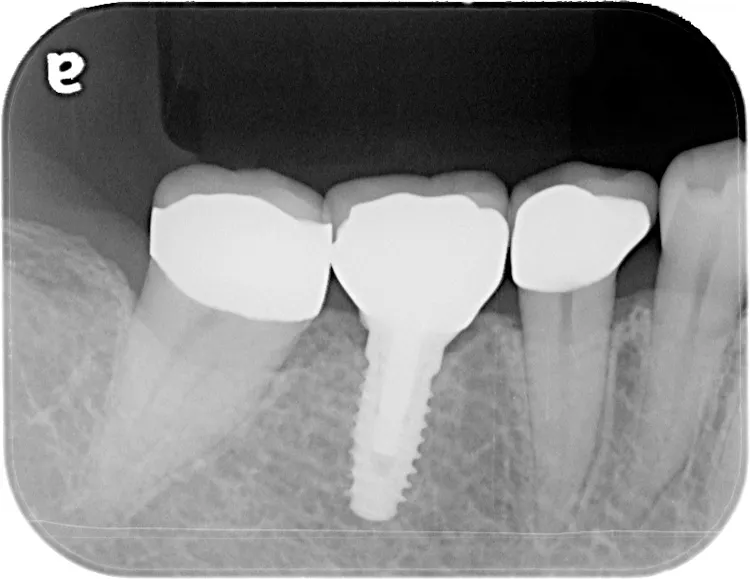

左下67 欠損に対してインプラント治療を行った症例

部分床義歯を使用していたが、どうしても慣れない上にしっかり噛むことができないためインプラント治療を希望